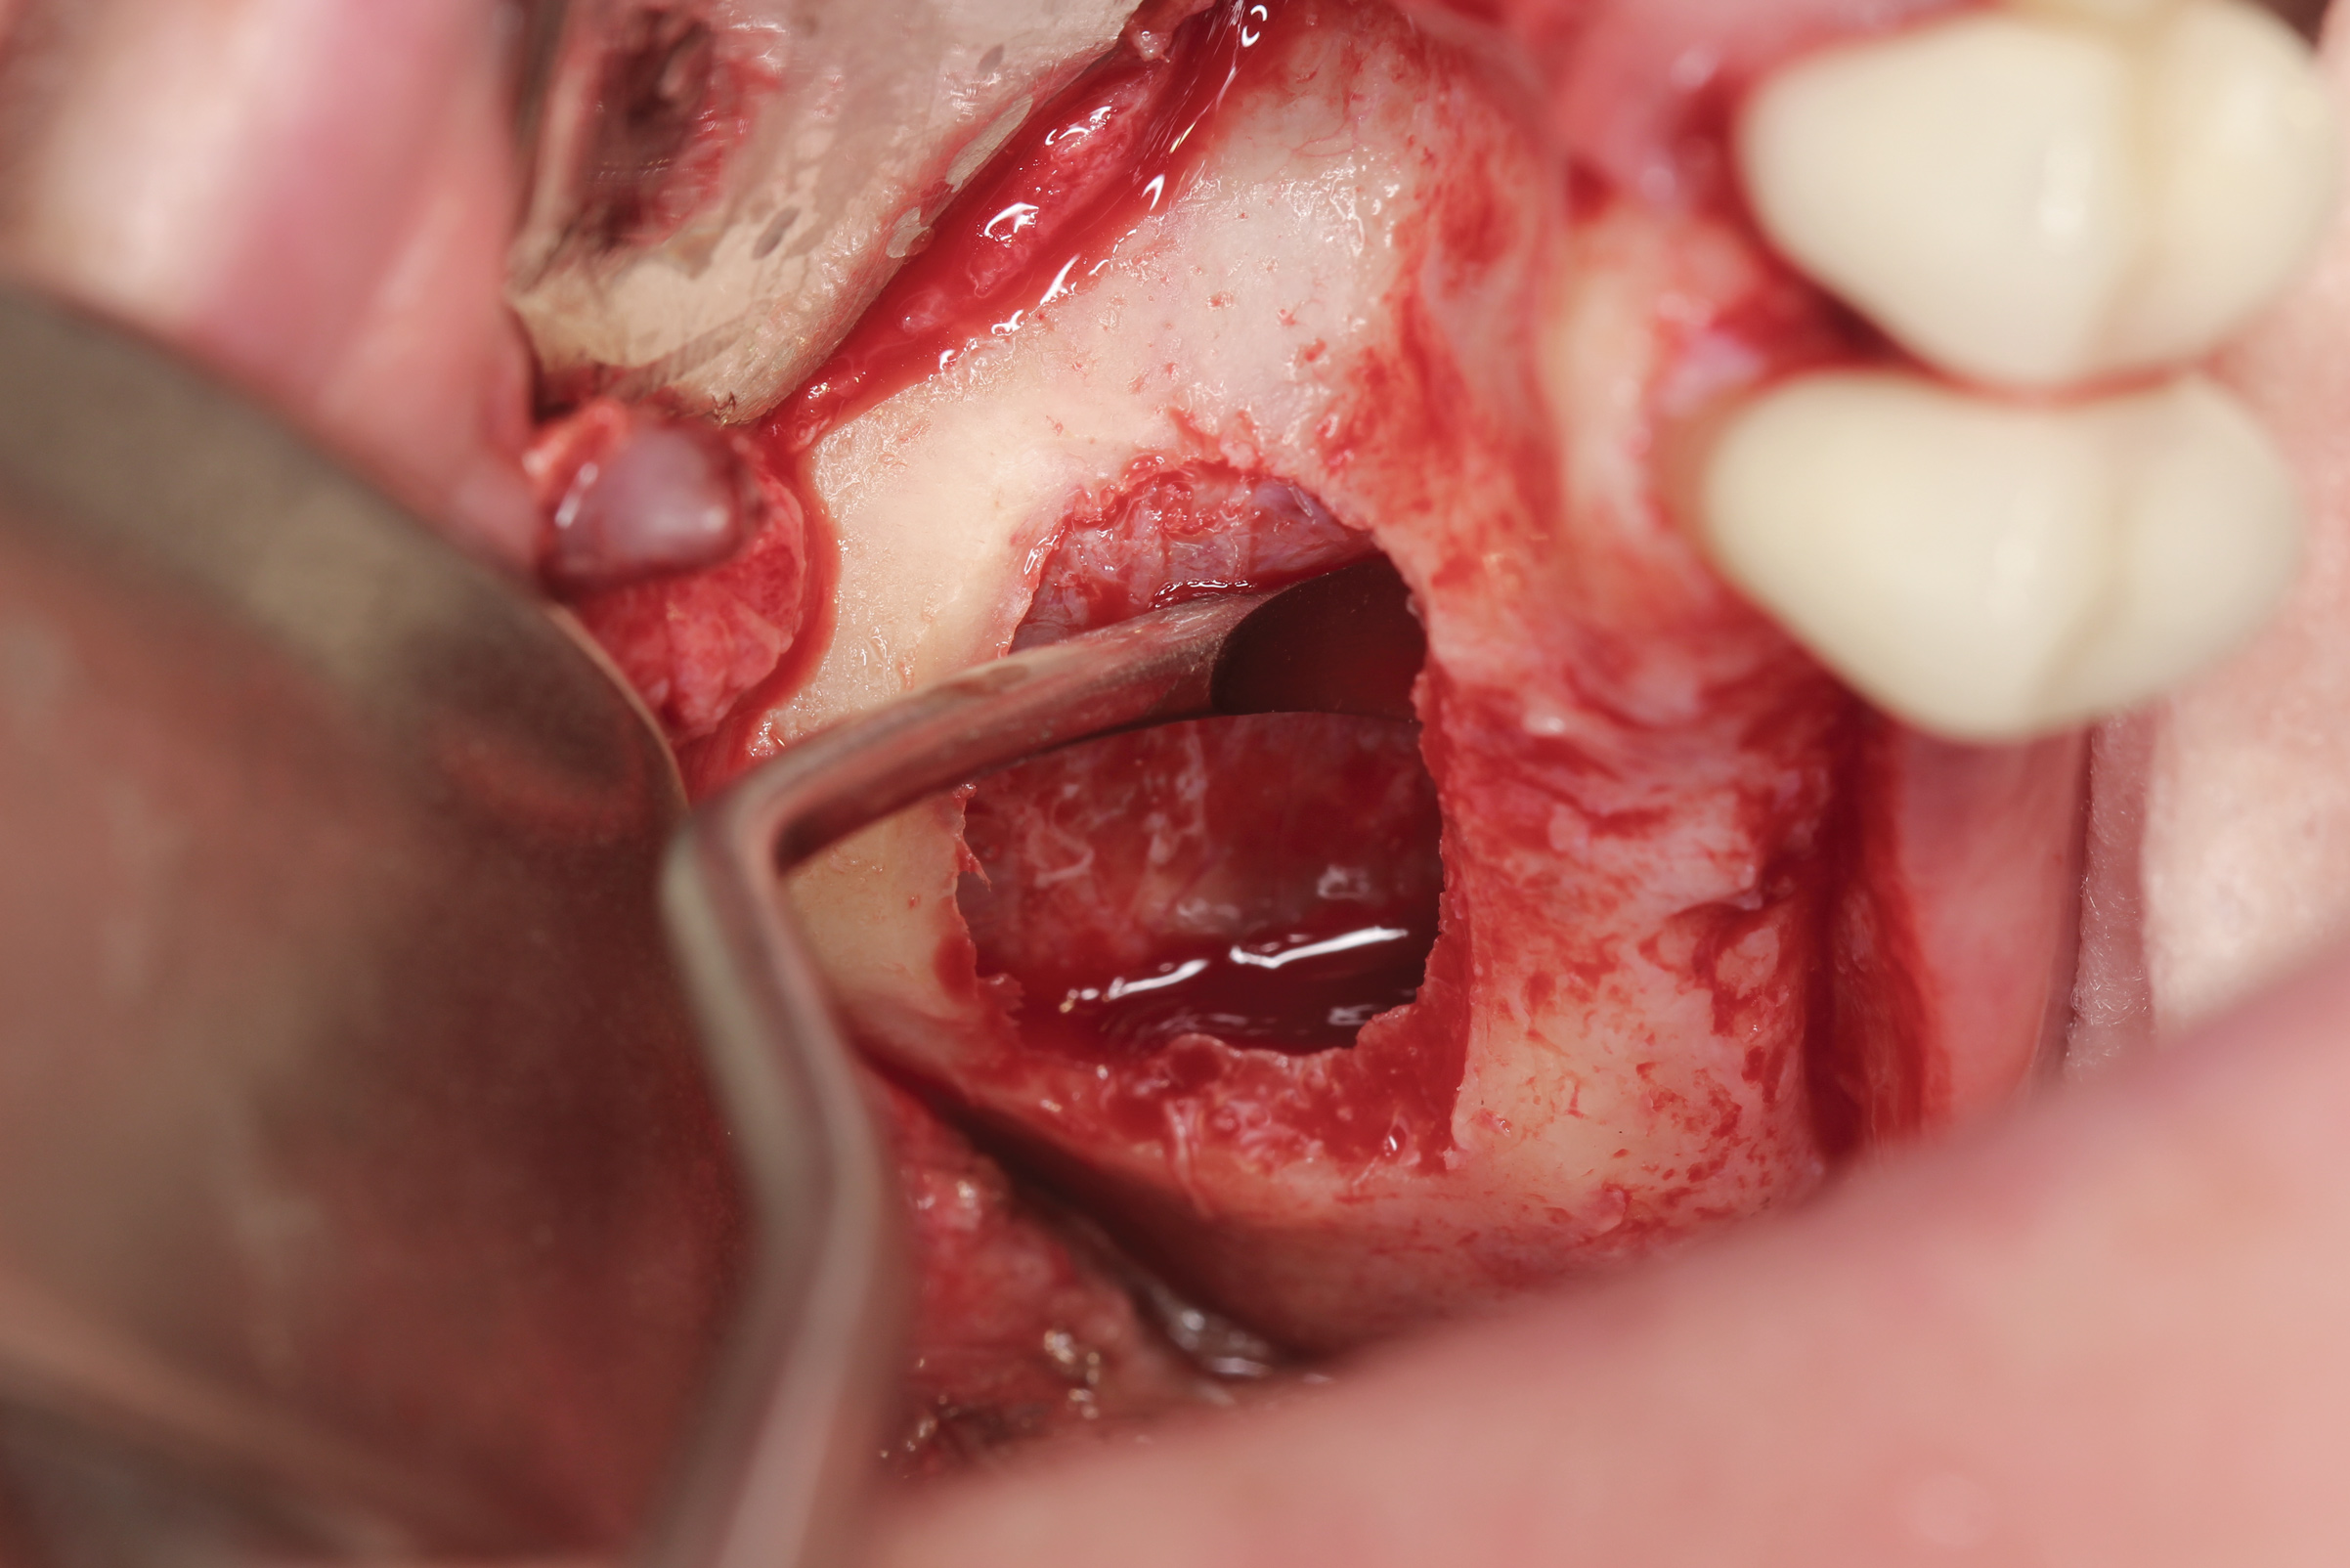

Fig 3. Lateral sinus augmentation; an initial window was created using a combination of a round fissure bur and, as shown, a piezosurgery device tip.

Figure 3